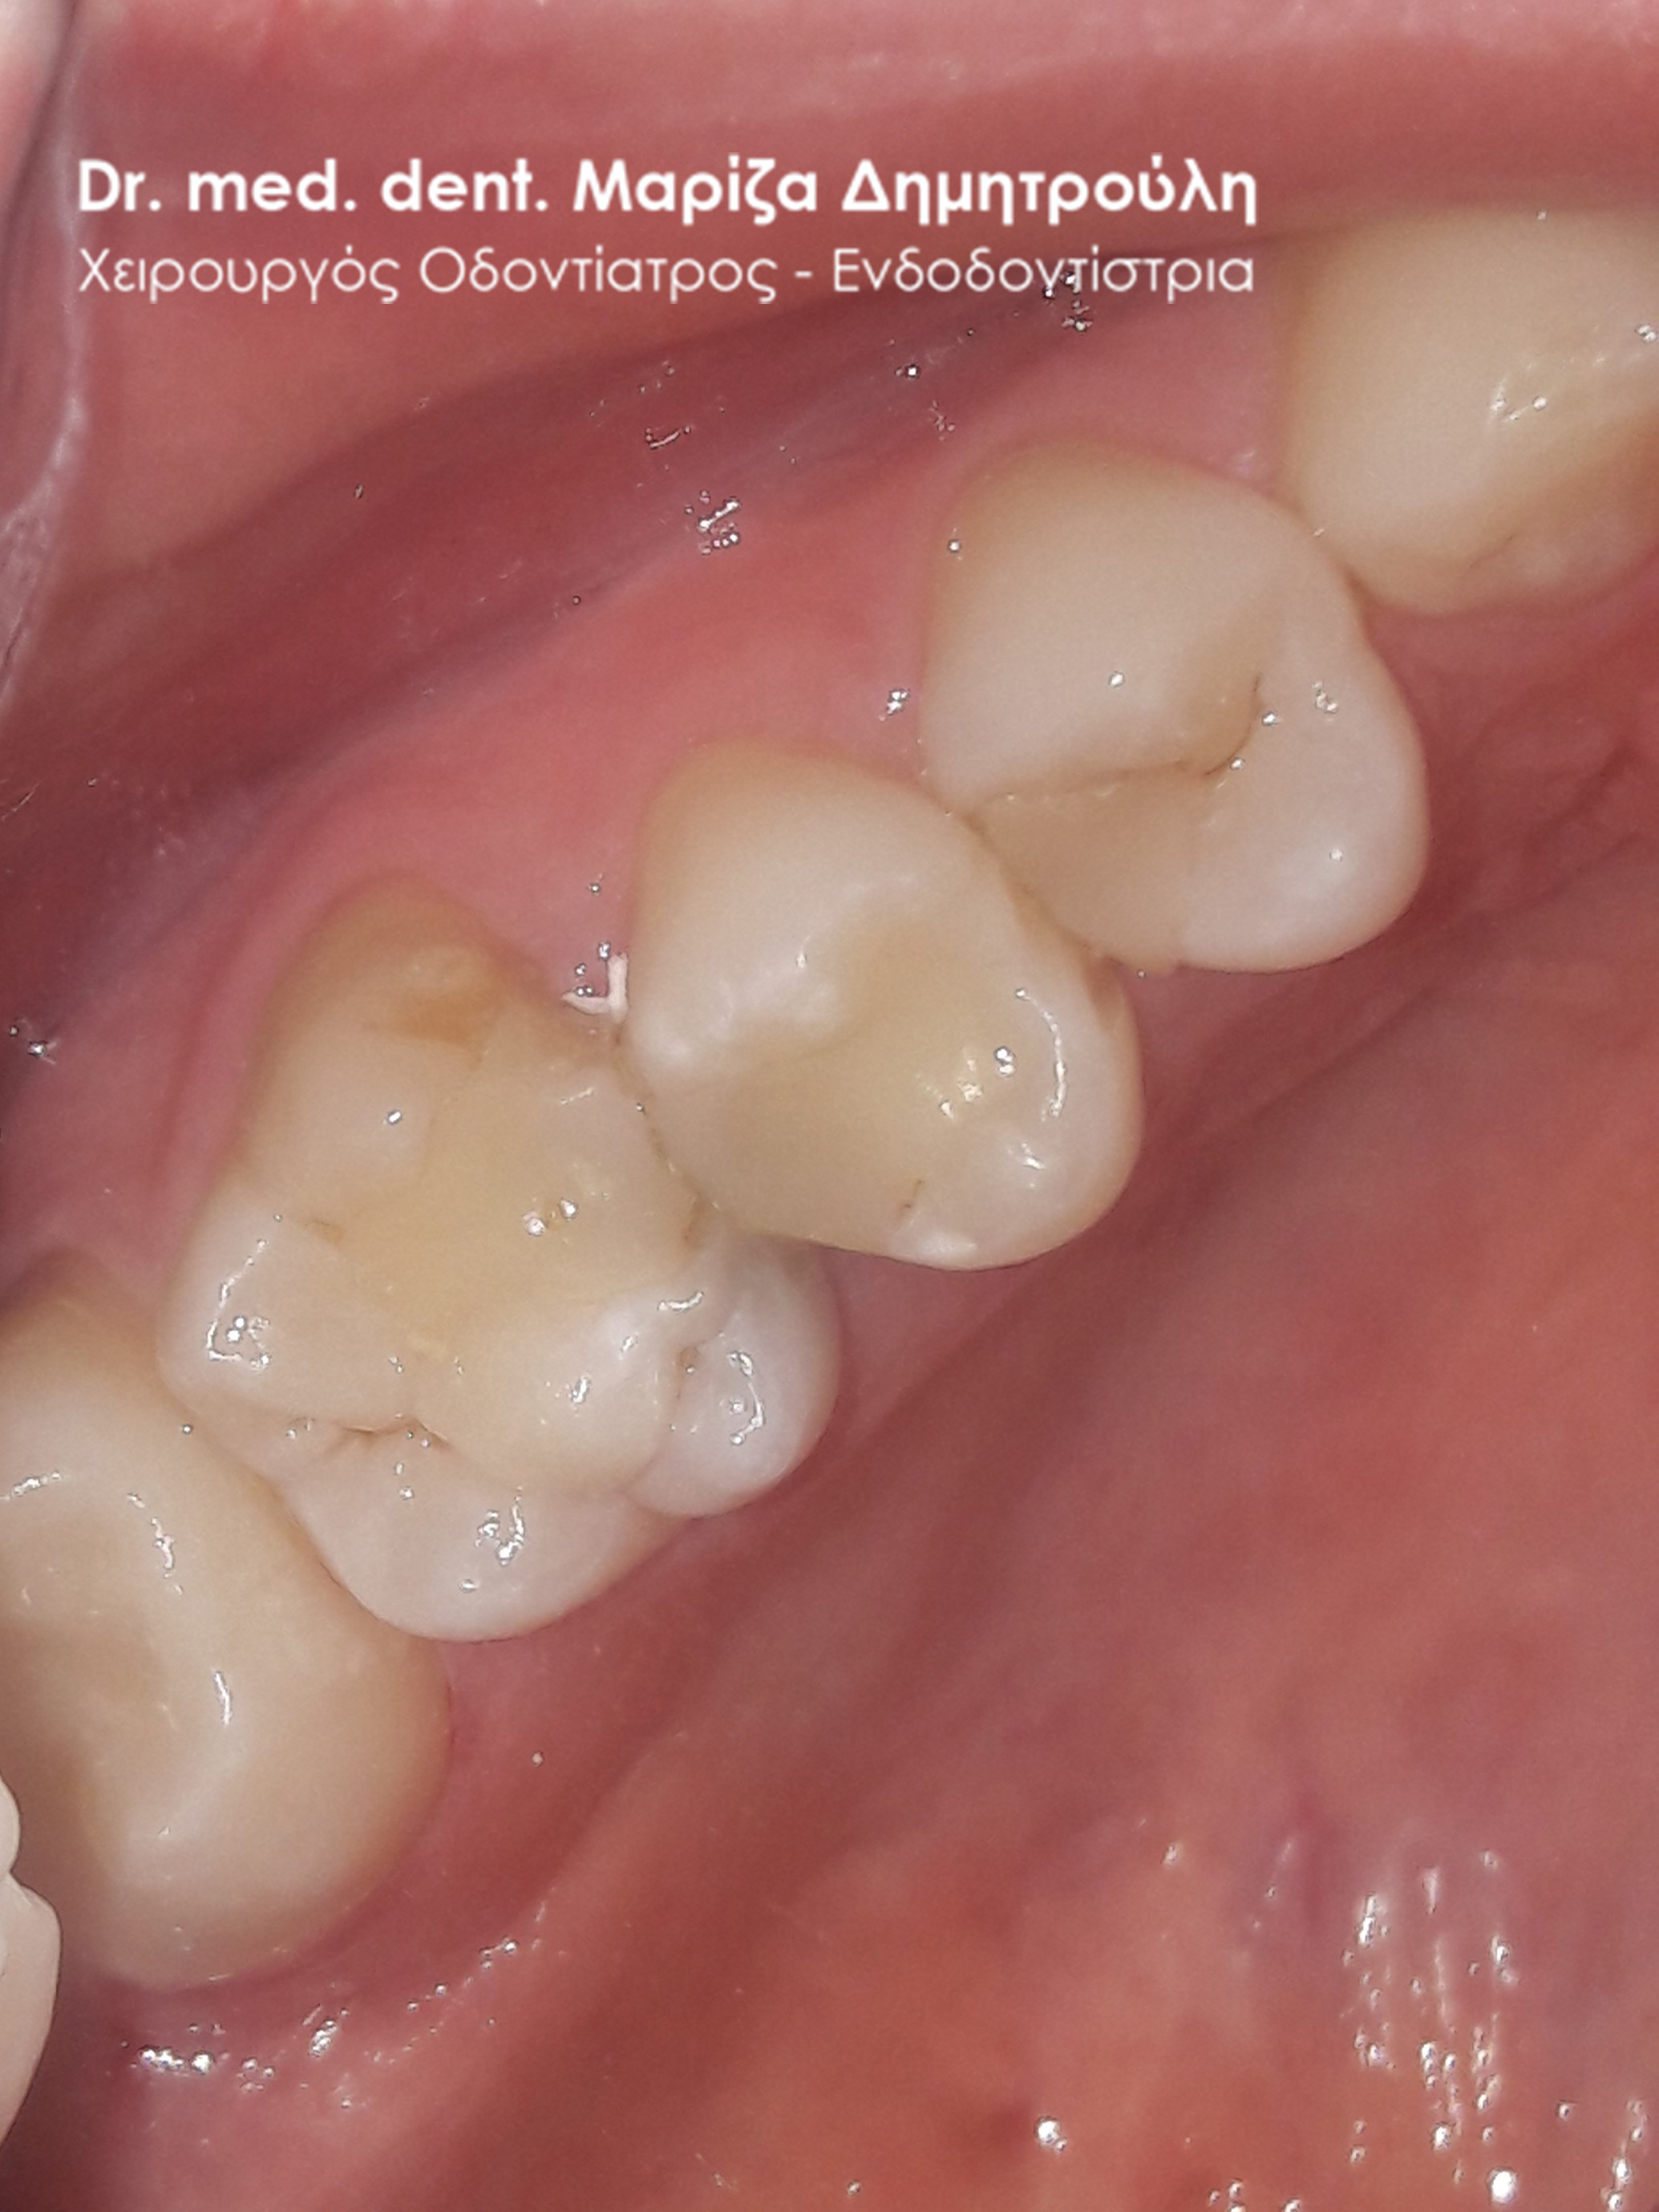

Ο ασθενής επιθυμούσε την αντικατάσταση των μαύρων σφραγισμάτων αμαλγάματος στον πρώτο δεξιό γομφίο και στο δεύτερο γομφίο με λευκά σφραγίσματα σύνθετης ρητίνης. Η θεραπεία πραγματοποιήθηκε με τη χρήση ελαστικού απομονωτήρα, όπως ορίζουν τα παγκόσμια πρωτόκολλα οδοντιατρικής για την αφαίρεση των μαύρων σφραγισμάτων. Όταν οι οδοντίατροι χρησιμοποιούν απομονωτήτρα κατά την αφαίρεση σφραγισμάτων αμαλγάματος, τότε ο ασθενής εισπνέει ελάχιστα και δεν καταπίνει τον υδράργυρο, που απελευθερώνεται κατά τη διαδικασία αυτή.

ΠΡΙΝ

META